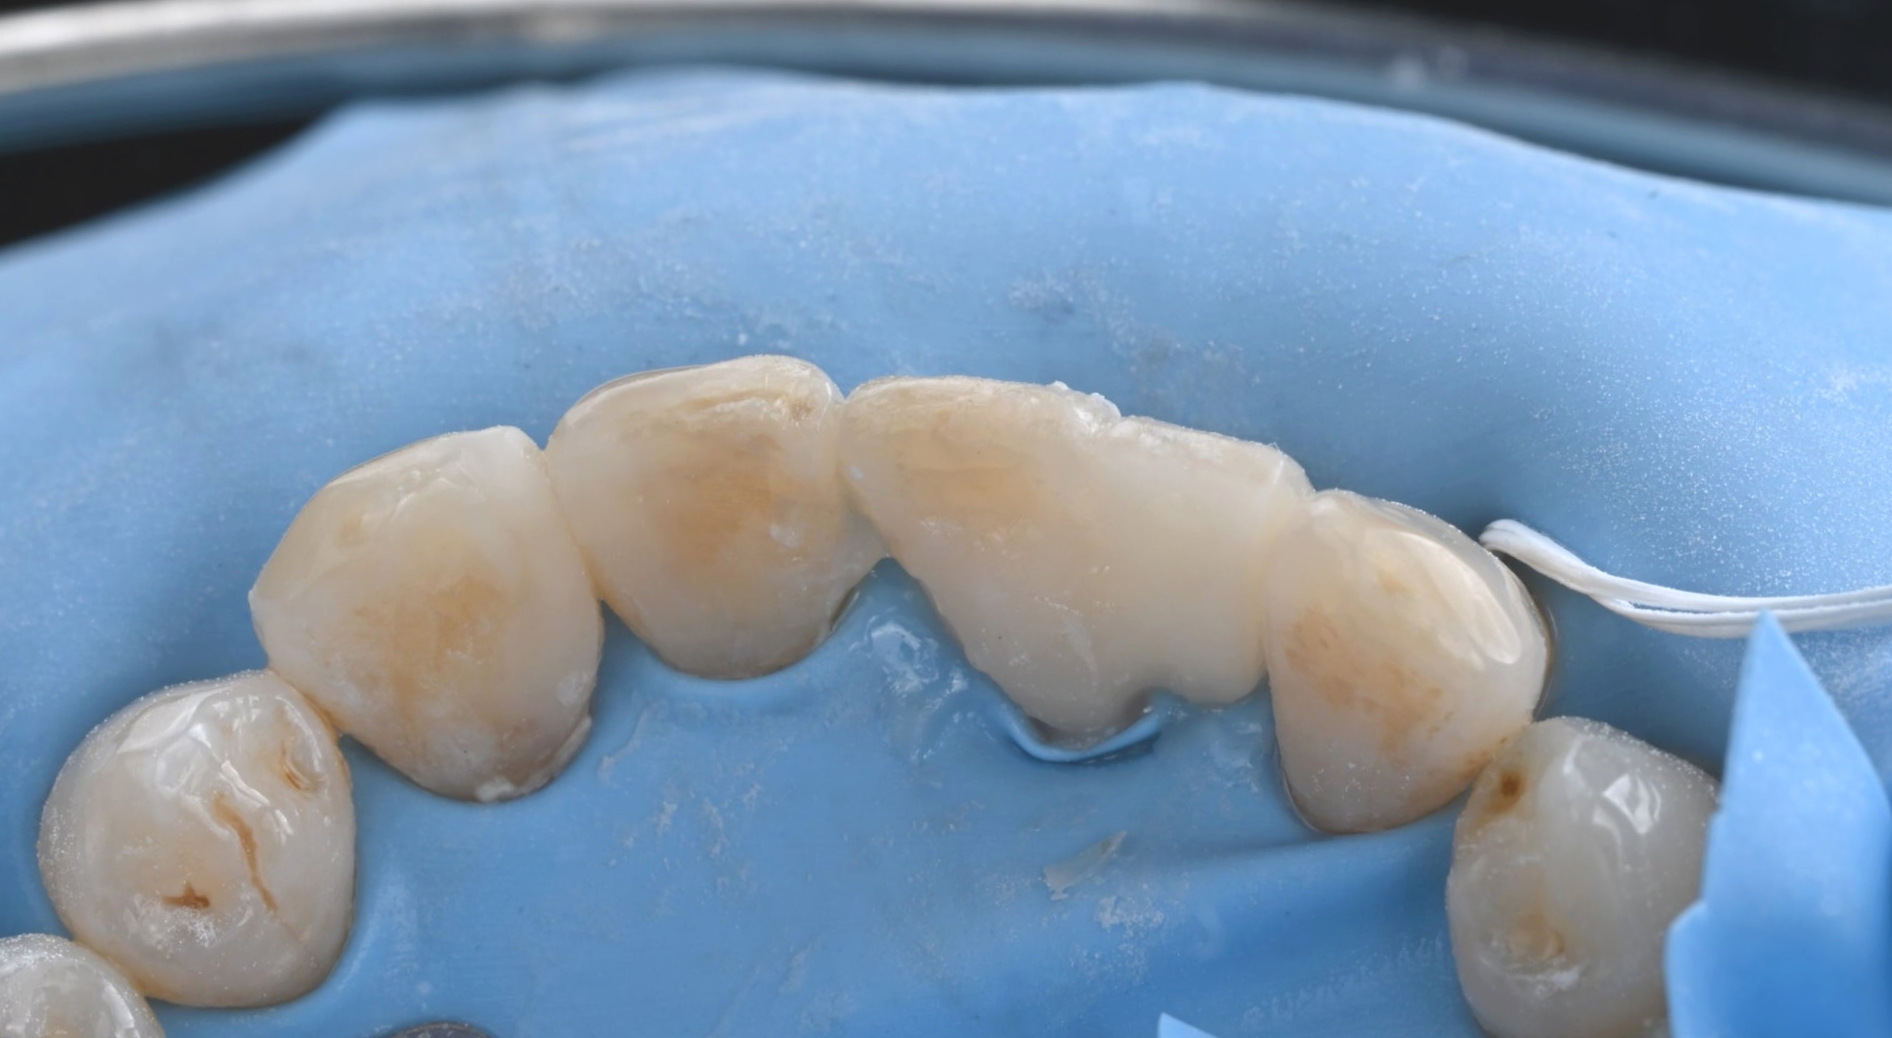

26.03.19

26.04.02 메릴랜드 브릿지 접착 준비

2) 정밀한 기공 제작

기공소장님과 긴밀히 소통하여

환자분의 치아 색상과 투명도를

자연치아와 유사하게 재현한

보철물을 의뢰했고, 정성스럽게 제작된

보철물을 확인했습니다.